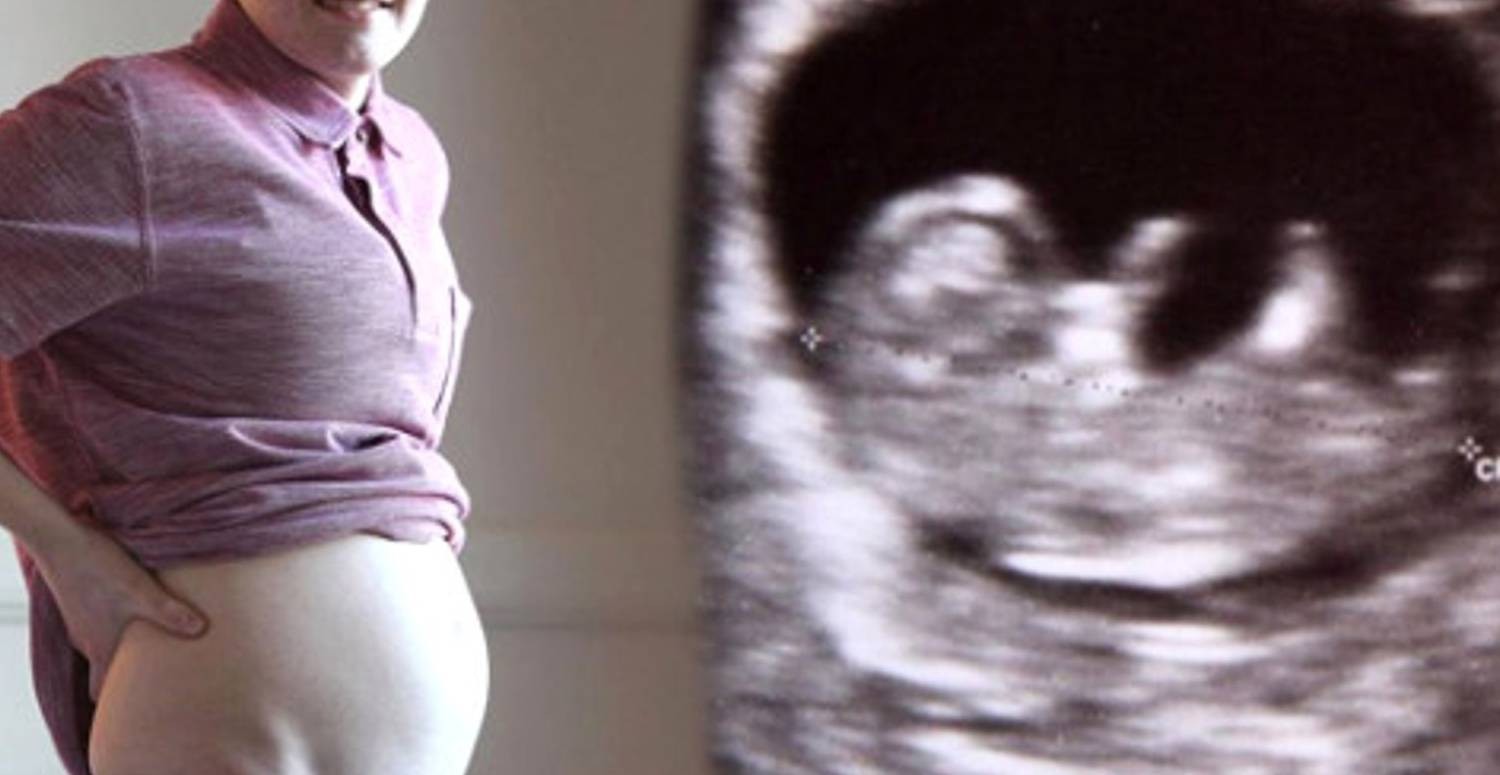

Erkekler hazır olun! Artık siz de hamile kalabileceksiniz

erkeklerde hamile olabilir

Y kromozomunun tamamen yok olacağı bu durumun doğurganlık sorunlarına neden olması yönünde iddialar ortaya atıldı. Erkeklerinde hamile kalabileceği yönünde bilgiler ortalıkta gezinirken Y kromozomunun işlevi değiştirilerek kadın çiftlerin veya kısır erkeklerin yardımlı üreme teknikleriyle gebe kalmasının mümkün olduğu düşünülüyor.